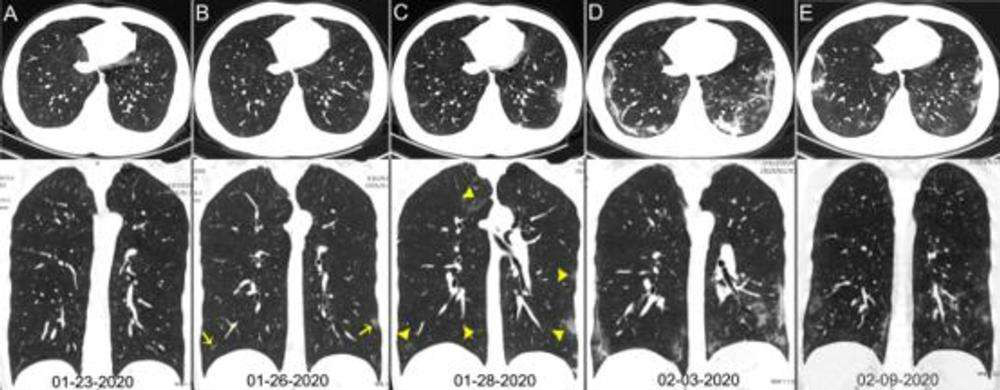

Por medio de las radiografías puede ser más difícil el diagnóstico de daños en el pulmón en un portador covid-19. Sin embargo, las tomografías muestran claramente los daños causados, como el realizado por un equipo médico responsable del estudio que analizó a pacientes de Wuhan, China.

Las imágenes muestran claramente, para especialistas, la evolución de la neumonía. Por eso, los investigadores concluyeron que la radiografía de tórax no es el examen ideal para el diagnóstico de la nueva enfermedad, sino la tomografía computarizada. Este último debe usarse en caso de duda en el momento del diagnóstico correcto de covid-19, si el médico lo considera necesario.